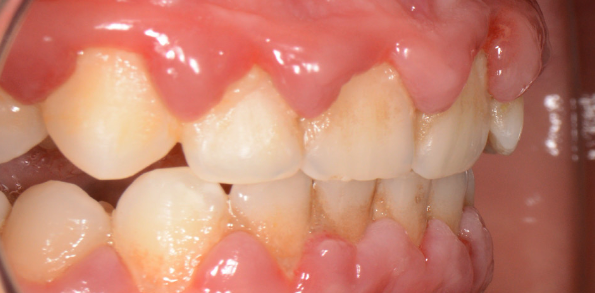

Trebuie avut în vedere faptul că starea dinților nu este întotdeauna concordantă cu starea țesuturilor parodontale. Deși prin prezența plăcii bacteriene și a tartrului dentar nu este afectat (încă) de carii sau complicații ale acestora, parodonțiul se poate afla într-o anumită stare de „îmbolnăvire” care variază de la o simplă gingivită până la o parodontită severă. De aceea, boala parodontală mai este numită malițios „boala dinților sănătoși”. Parodonțiul, adică structura de menținere a dintelui pe arcadă, este alcătuit din mai multe structuri: osul alveolar și ligamentele parodontale care creează o legătură între dinte, gingie și osul alveolar.

Mulți pacienți tind să amâne vizita la medic, pentru că de cele mai multe ori nu este prezentă senzația dureroasă. Placa bacteriană greu accesibilă și mai ales tartrul pot fi îndepărtate printr-un simplu detartraj cu ultrasunete și un periaj dentar profesional efectuate o dată la 6 luni de către medicul dentist. Spațiile mai greu accesibile cu tartru aderent se vor igieniza mecanic cu instrumente speciale de detartraj: chiurete parodontale și scalare. Prin îndepărtarea plăcii bacteriene și a tartrului și prin menținerea unei igiene corecte, semnele de afectare gingivală vor dispărea, iar gingia își va recăpăta starea de sănătate inițială. Gingivita simplă netratată va evolua în anumite zone ale cavității orale spre boala parodontală. Netratată, aceasta se va extinde treptat la tot mai mulți dinți, având o evoluție cronică și într-un final, după distrucții extinse, se vor pierde dinții. Tratamentul bolii parodontale este mult mai complicat și mai laborios decât al unei gingivite simple, de aceea este foarte important să se intervină în stadii cât mai incipiente ale bolii. (Fig. 5.1.5, 5.1.6, 5.1.7)